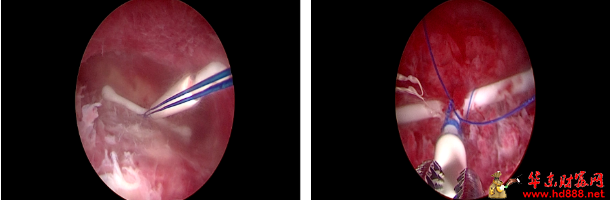

偶然得知阜阳市妇女儿童医院有曼月环固定缝合术,王女士抱着试一试的想法挂了号,在医生的建议下,她接受了宫腔镜下曼月乐环缝合固定术。手术中,医生通过宫腔镜直视子宫内部,将曼月乐环放置到位后用缝合线固定于子宫壁。

02 宫腔镜下曼月乐环缝合固定术的操作要点 该手术为经自然腔道微创操作,无需开腹,全程在宫腔镜直视下完成,核心步骤如下: 1. 术前评估:经阴道超声测量宫腔深度、评估腺肌病灶范围,排除宫腔粘连、黏膜下肌瘤等合并症,完善术前准备。 2. 麻醉与置镜:静脉麻醉后置入宫腔镜,全面探查宫腔,定位宫底安全固定区。 3. 精准放置与缝合:将曼月乐环置于宫底正中,用可吸收缝线或不可吸收缝线,将环体纵臂/尾丝与宫底肌层缝合固定,镜下完成打结,线结埋入肌层。 4. 术后核查:镜下确认环位正常、固定牢固,无出血与穿孔,手术结束。 手术时长约15-30分钟,创伤小、出血少,术后当日可下床活动,多数患者次日即可出院。